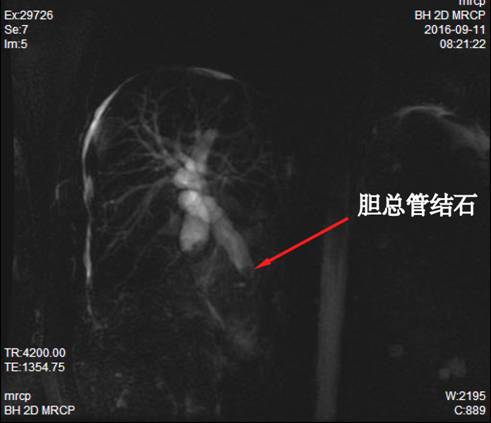

患者,男,56岁,因“腹痛、身黄眼黄2周”入院。

入院诊断:胆总管结石,胆囊结石伴胆囊炎,酒精性肝硬化失代偿期。

诊疗过程:因重度凝血功能障碍,予以外科手术或内镜下治疗均有发生不可控制的大出血。予以抗感染、保肝及经皮经肝胆囊穿刺引流术等保守治疗3个月,凝血功能有所好转后抓住手术时机,立即行ERCP,术中见结石嵌顿于十二指肠乳头(胆总管末端开口处),立即予以针刀切开十二指肠乳头,顺利取出胆总管结石,解除长达3个月的胆总管梗阻,术后患者很快就拔除胆囊穿刺管,恢复正常生活。

术前MRCP